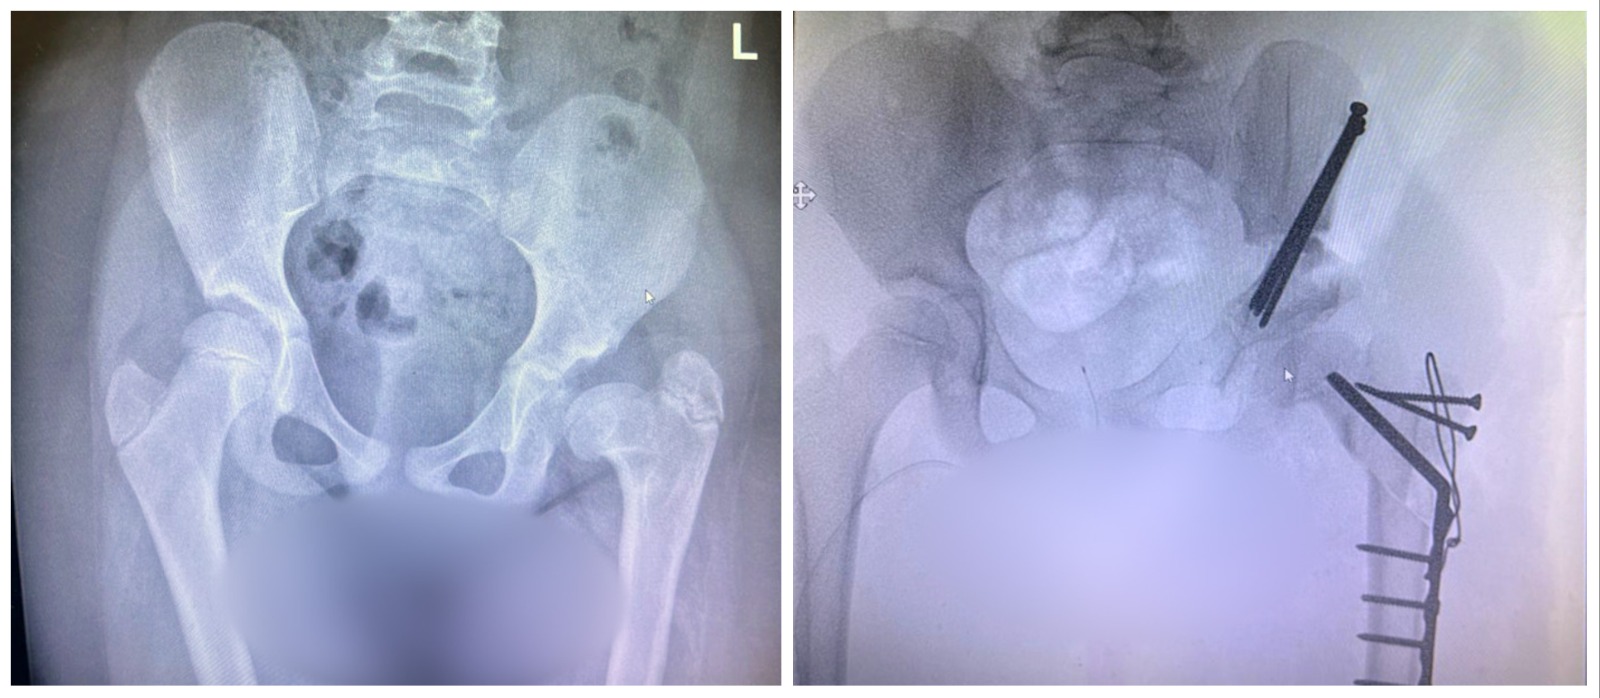

Amal was born with a congenital deformity – a dislocated hip. Over time, the deformity had left her with a severe limp and one leg markedly shorter than the other. Even after multiple surgeries, Amal was in constant pain that affected every aspect of her life. However, her mother would not give up and made every effort to find a solution elsewhere – something or someone that could improve Amal’s quality of life.

It took many months to arrange for Amal’s arrival in Israel and her surgery at Rambam. Finally, a few days ago, Professor Eidelman and his multidisciplinary team performed the complex procedure of lengthening her thigh bone (femur). “Amal’s surgery was challenging, but we were successful, and it ended well,” Eidelman adds. “We repaired her femur with a plate, screws, and an implant. Following the surgery, we immediately noticed an improvement in her condition. She can now walk again, has less pain, and is able to enjoy her life. Amal is calm and her parents are delighted. After being discharged, the family returned to Jordan, and in six-weeks, Amal will return to Israel for a follow-up visit at Rambam. I am very optimistic.”